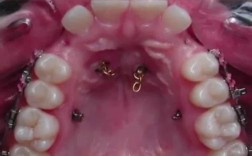

- 多生牙或埋伏阻生牙: 如果存在这些异常牙齿,阻碍了正常牙齿的排列或导致畸形,拔除它们是必要的,但这属于病理情况而非常规正畸拔牙。

- 最常拔的是双尖牙(前磨牙),尤其是第一前磨牙。 拔4颗(上下左右各一颗)是最常见的方案。